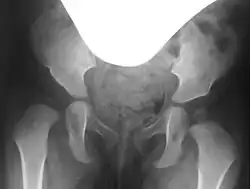

Lateral coverage is measured using the acetabular angle (AC angle) on a pelvic X-ray, defined as the angle between a horizontal line through the Y-sutures and a line along the acetabular rim. In healthy newborns, the AC angle is approximately 25°, decreasing to about 15° by age 6 and 11–12° by age 12.[6] Acetabuloplasty aims to correct the AC angle to these physiological values, achieving an anatomical reconstruction.[6]

Preoperative planning involves conventional pelvic X-rays, including pelvic overview and Rippstein view images, to assess joint misalignment, severity, and surgical planning. Rippstein views provide a lateral projection of the femoral necks.[7][8]